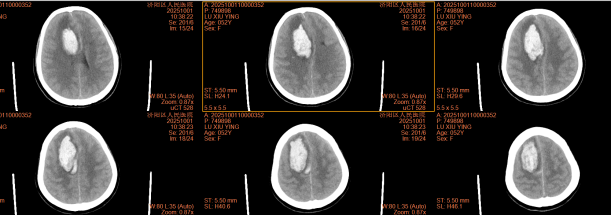

患者为52岁女性,因突发左侧肢体活动不灵伴意识障碍2小时入院。颅脑CT检查显示患者右额叶脑出血,出血量约32ml,血肿压迫周围脑组织,病情危急,若不及时干预,可能导致永久性神经功能损伤甚至危及生命。

术前CT ↑